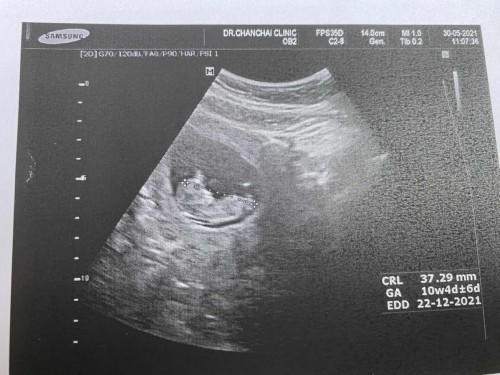

ท้องแรก อายุ 30ปี ค่ะตั้งครรภ์ได้11สัปดาห์เป็นความดันโลหิตสูงหมอบอกหน้าเป็นห่วงและผลการซาวด์หมอบอกว่าน้องคอหนา แม่นี่เครียดเลย -ความดันสูงแม่ๆคนไหนเป็นหรือมีตัวช่วยแนะนำหน่อยค่ะ -ลูกคอหนา เราต้องตรวจดาว์นไหมค่ะ

ปกติคอหนาเสี่ยงดาวน์ซินโดรมอยู่แล้วค่ะ ถ้าแม่อายุครรภ์ไม่เกิน 20 week ยังตรวจได้อยู่ค่ะ ถ้าเกินนี้ตรวจไม่ได้ ส่วนความดันแม่ต้องให้คุณหมอประเมินและจ่ายยามาทาน ต้องใกล้ชิดหมอมากๆ การดูแลตัวเองก็... 1.ควบคุมน้ำหนักตัว ... 2.รับประทานอาหารที่ไม่เค็มจัด ... 3.งดการดื่มแอลกอฮอล์ ... 4.งดสูบบุหรี่ ... 5.พักผ่อนให้เพียงพอ ... 6.ออกกำลังกายเป็นประจำ ...